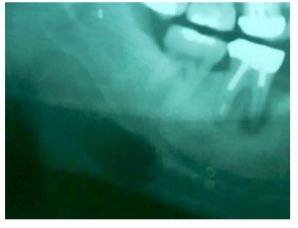

26一位 66 歲男性病患主訴下顎右側臼齒區不適,並且有瘻管產生,環口攝影發現病患右下第一大臼齒牙根部有一 X 光可透過區(radiolucence)(如下圖),最有可能的臨床診斷為何? (A)根尖膿腫(periapical abscess) (B)牙周囊腫(periodontal cyst) (C)外傷性骨囊腫(traumatic bone cyst) (D)牙齦囊腫(gingival cyst)